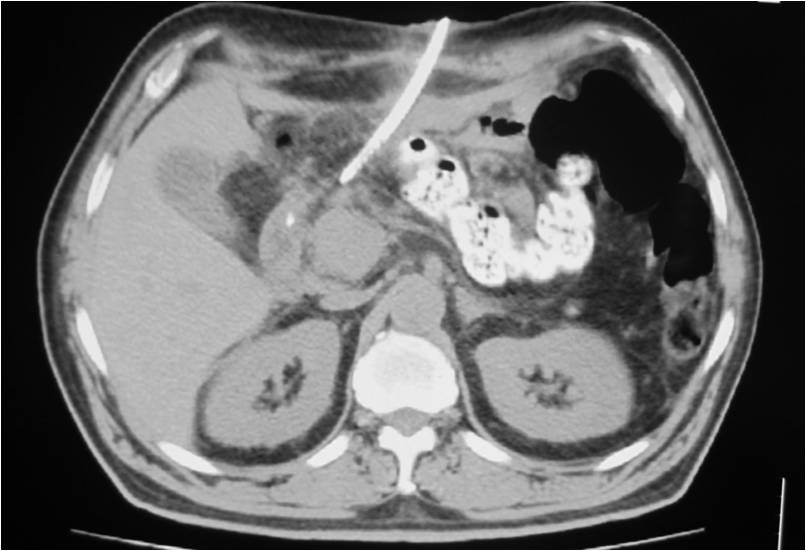

- Placement of a nephrostomy and sump caheter through the greater sciatic foramen into a deep pelvic abscess.